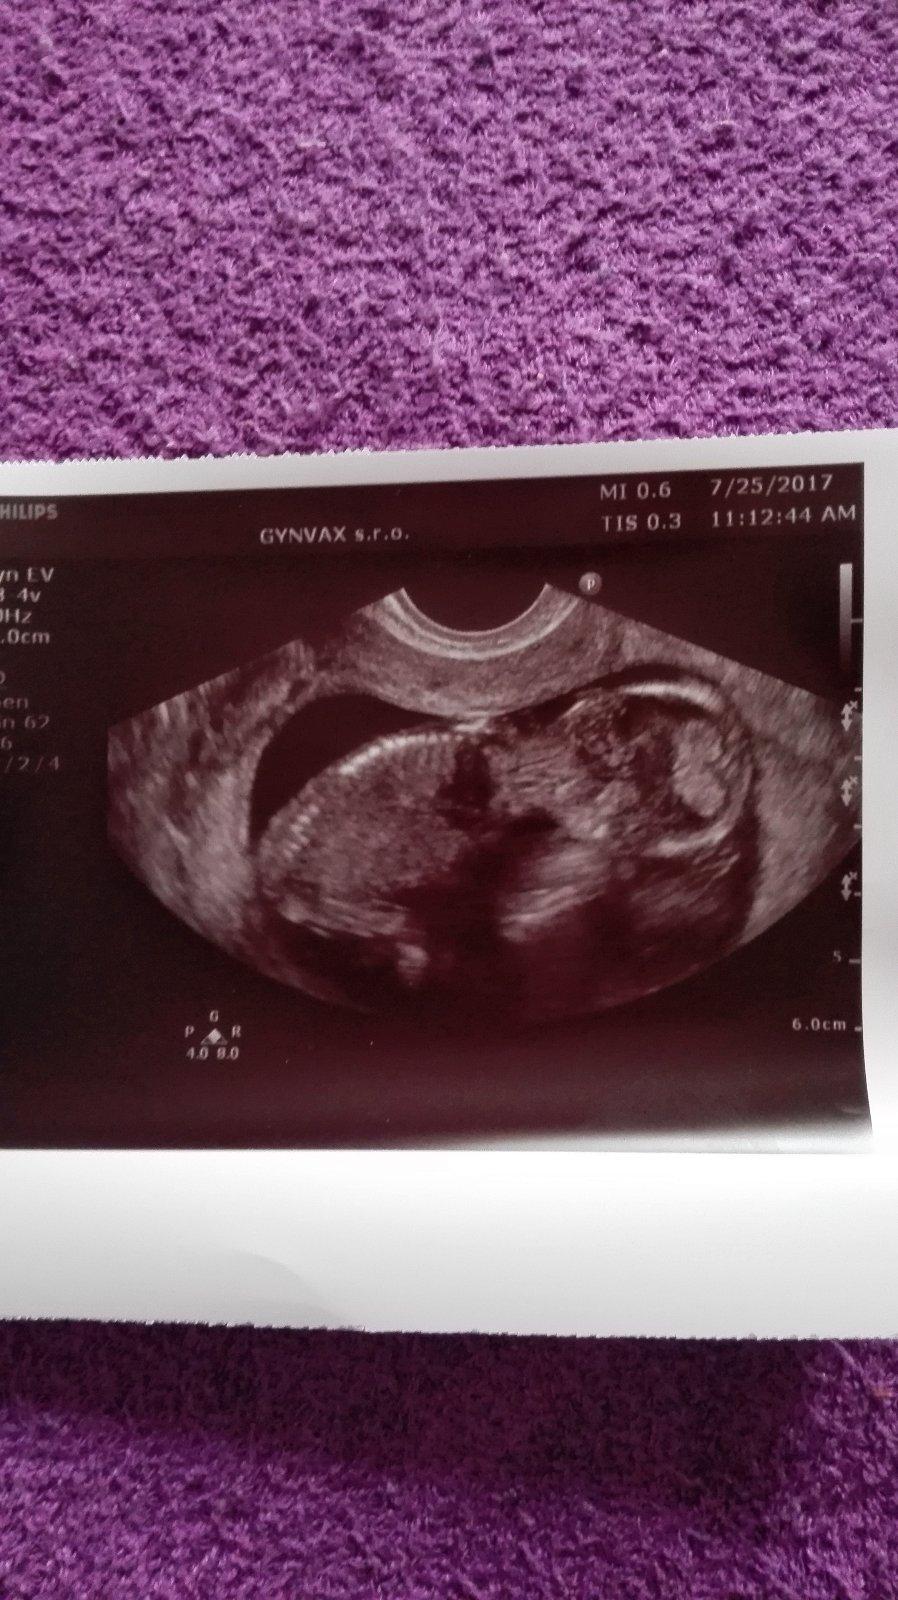

Ahojte kočky tak dnes som 32DC (16DPO) a teraz som už konečne pokojnejšia a začínam sa tešiť že čiaročka je silná....no kuknite

@alilka wau teším sa veľmi...nech len rastiete !!!To sú riadne kolajnice,koľky den cyklu si?

@ejuska2586 máš tiež krásne kolajnice....už aj ja chcem takeeee,teším sa baby,prajem vám len už preberanie na váhe